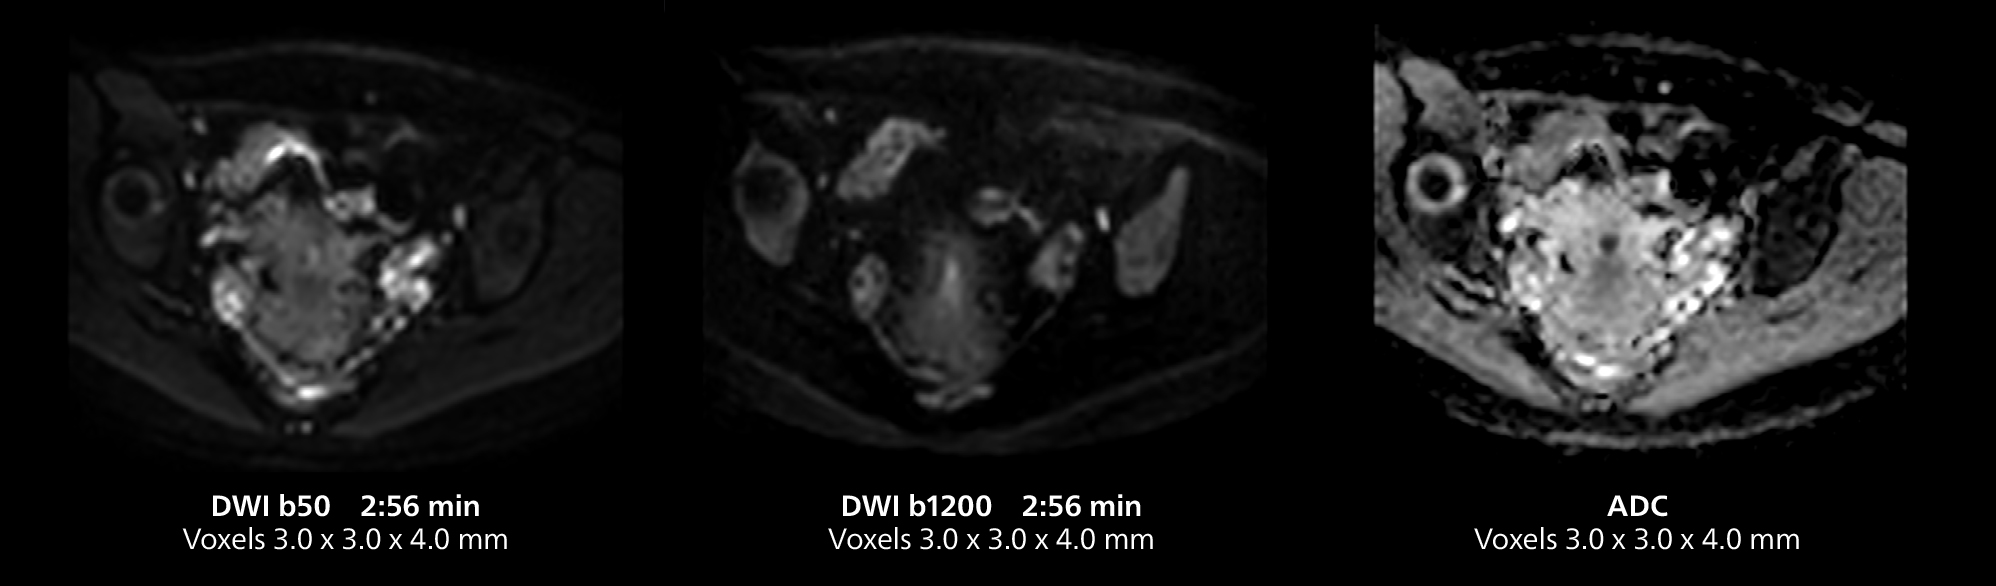

Dr. Gellée highlights the robust free-breathing scans as “the feature that makes the biggest difference in my daily work. The 3D free breathing sequences are very reproducible, and the axial acquisition is very good. For example, in endometriosis, which is one of my focus areas, it provides high contrast and good resolution so that I can see small details. We also use free breathing for liver and pancreas imaging. In multi-phase liver studies, 4D Free Breathing delivers 3-second temporal resolution, making a dynamic scan with more than one arterial phase possible.”

This MRI case illustrates good resolution and imaging quality obtained within reasonable scan times using the MR 5300 1.5T system with the anterior torso cardiac coil that allows use of a large field of view (FOV).